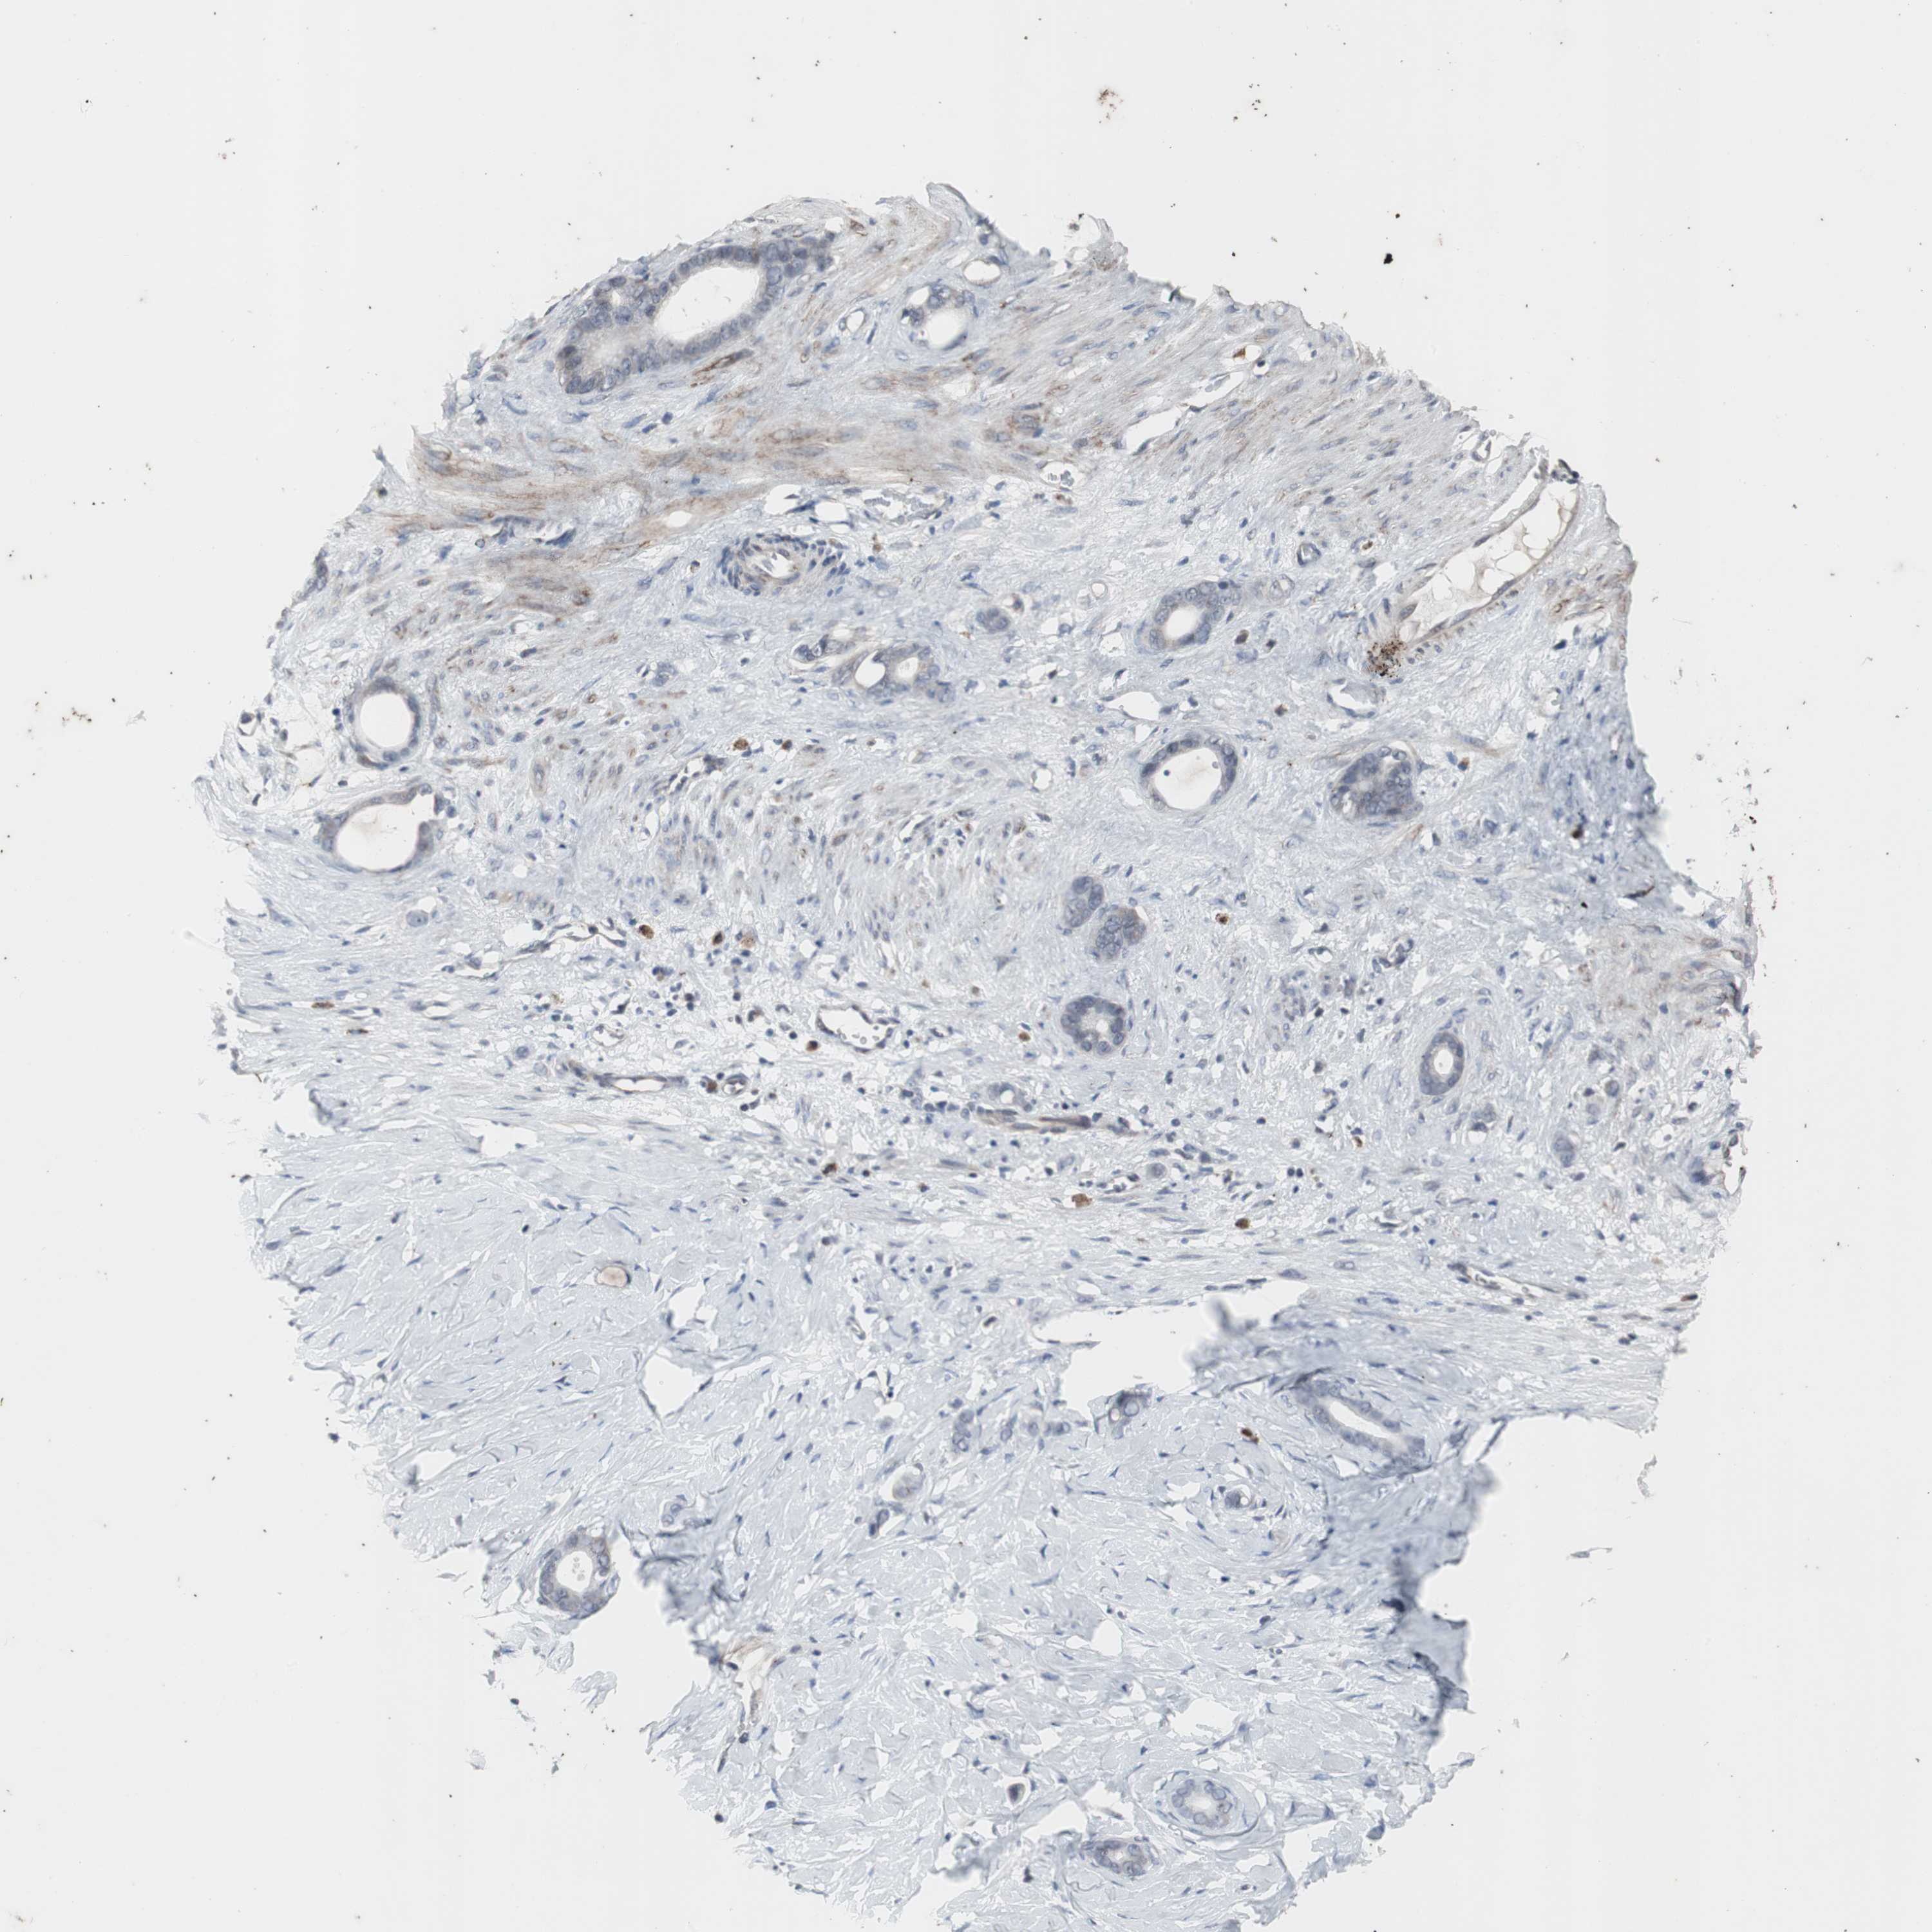

STOMACH CANCER - Protein expressioni

A mouse-over function shows sample information and annotation data. Click on an image to view it in a full screen mode. Samples can be filtered based on level of antibody staining by selecting one or several of the following categories: high, medium, low and not detected. The assay and annotation is described here.

Note that samples used for immunohistochemistry by the Human Protein Atlas do not correspond to samples in the TCGA dataset.

Antibody stainingi

Antibody staining in the annotated cell types in the current human tissue is reported as not detected, low, medium, or high, based on conventional immunohistochemistry profiling in selected tissues. This score is based on the combination of the staining intensity and fraction of stained cells.

Each image is clickable and will lead to virtual microscopy that enables deeper exploration of all samples and also displays staining intensity scores, fraction scores and subcellular localization as well as patient and tissue information for each sample.

Antibody CAB005337

Staining

High

Medium

Low

Not detected

Intensity

Strong

Moderate

Weak

Negative

Quantity

>75%

75%-25%

<25%

None

Location

Nuclear

Cytoplasmic/membranous

Cytoplasmic/membranous,nuclear

Adenocarcinoma, NOS

Adenocarcinoma, High grade